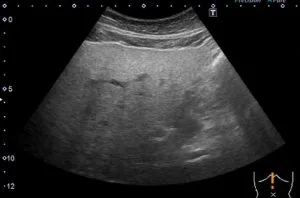

血液検査で肝機能を調べるほか、飲酒の有無の確認、超音波検査やCT検査などの画像検査により、肝臓の大きさや脂肪のつき具合を見て診断します。

超音波検査では右図のように肝臓が白く見えるのが特徴です。